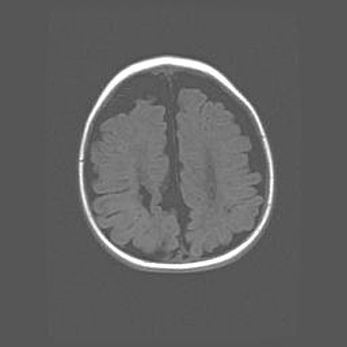

Церебральная ишемия II.

Возраст: 7 дней

Вес: 3350 г

Пол: женский

Окружность головы: 35 см

Срок гестации: 39 недель

Ишемия головного мозга – это состояние, которое развивается в ответ на кислородное голодание вследствие недостаточного мозгового кровообращения. У новорожденных она является следствием дефицита кислорода, что ведет к метаболическим расстройствам различной степени тяжести в тканях головного мозга, в том числе к развитию коагуляционных некрозов и гибели нейронов.